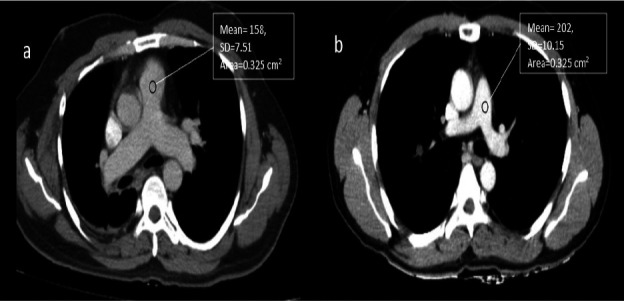

Methods: Group A consisted of 40 patients who underwent SD CECT thorax (120 kVp, 60 ml), while Group B included 40 patients who underwent LD-LV CECT thorax (80 kVp, 40 ml). All CECT thorax scans were performed using a 128-slice Incisive CT (Philips Healthcare Systems). A qualitative analysis of thoracic structures in both the lung and mediastinal windows was performed. Quantitative parameters, including Hounsfield units (HU) for the pulmonary artery (CTPA) and infraspinatus muscle (CTISM), noise (SD), and contrast-to-noise ratio (CNR), were also assessed. The Mann-Whitney U test and independent t-test were used to compare IQ and radiation dose between the two groups.

Results: Qualitative analysis of thoracic structures in the lung and mediastinal windows revealed no significant difference (p > 0.001) between the two groups. Quantitative parameters, such as CTPA, CTISM, and CNR, showed statistically significant differences (p < 0.001), with higher values observed in the LD-LV group compared to the SD group. The effective dose (ED) was reduced by 65.2% in the LD-LV group.